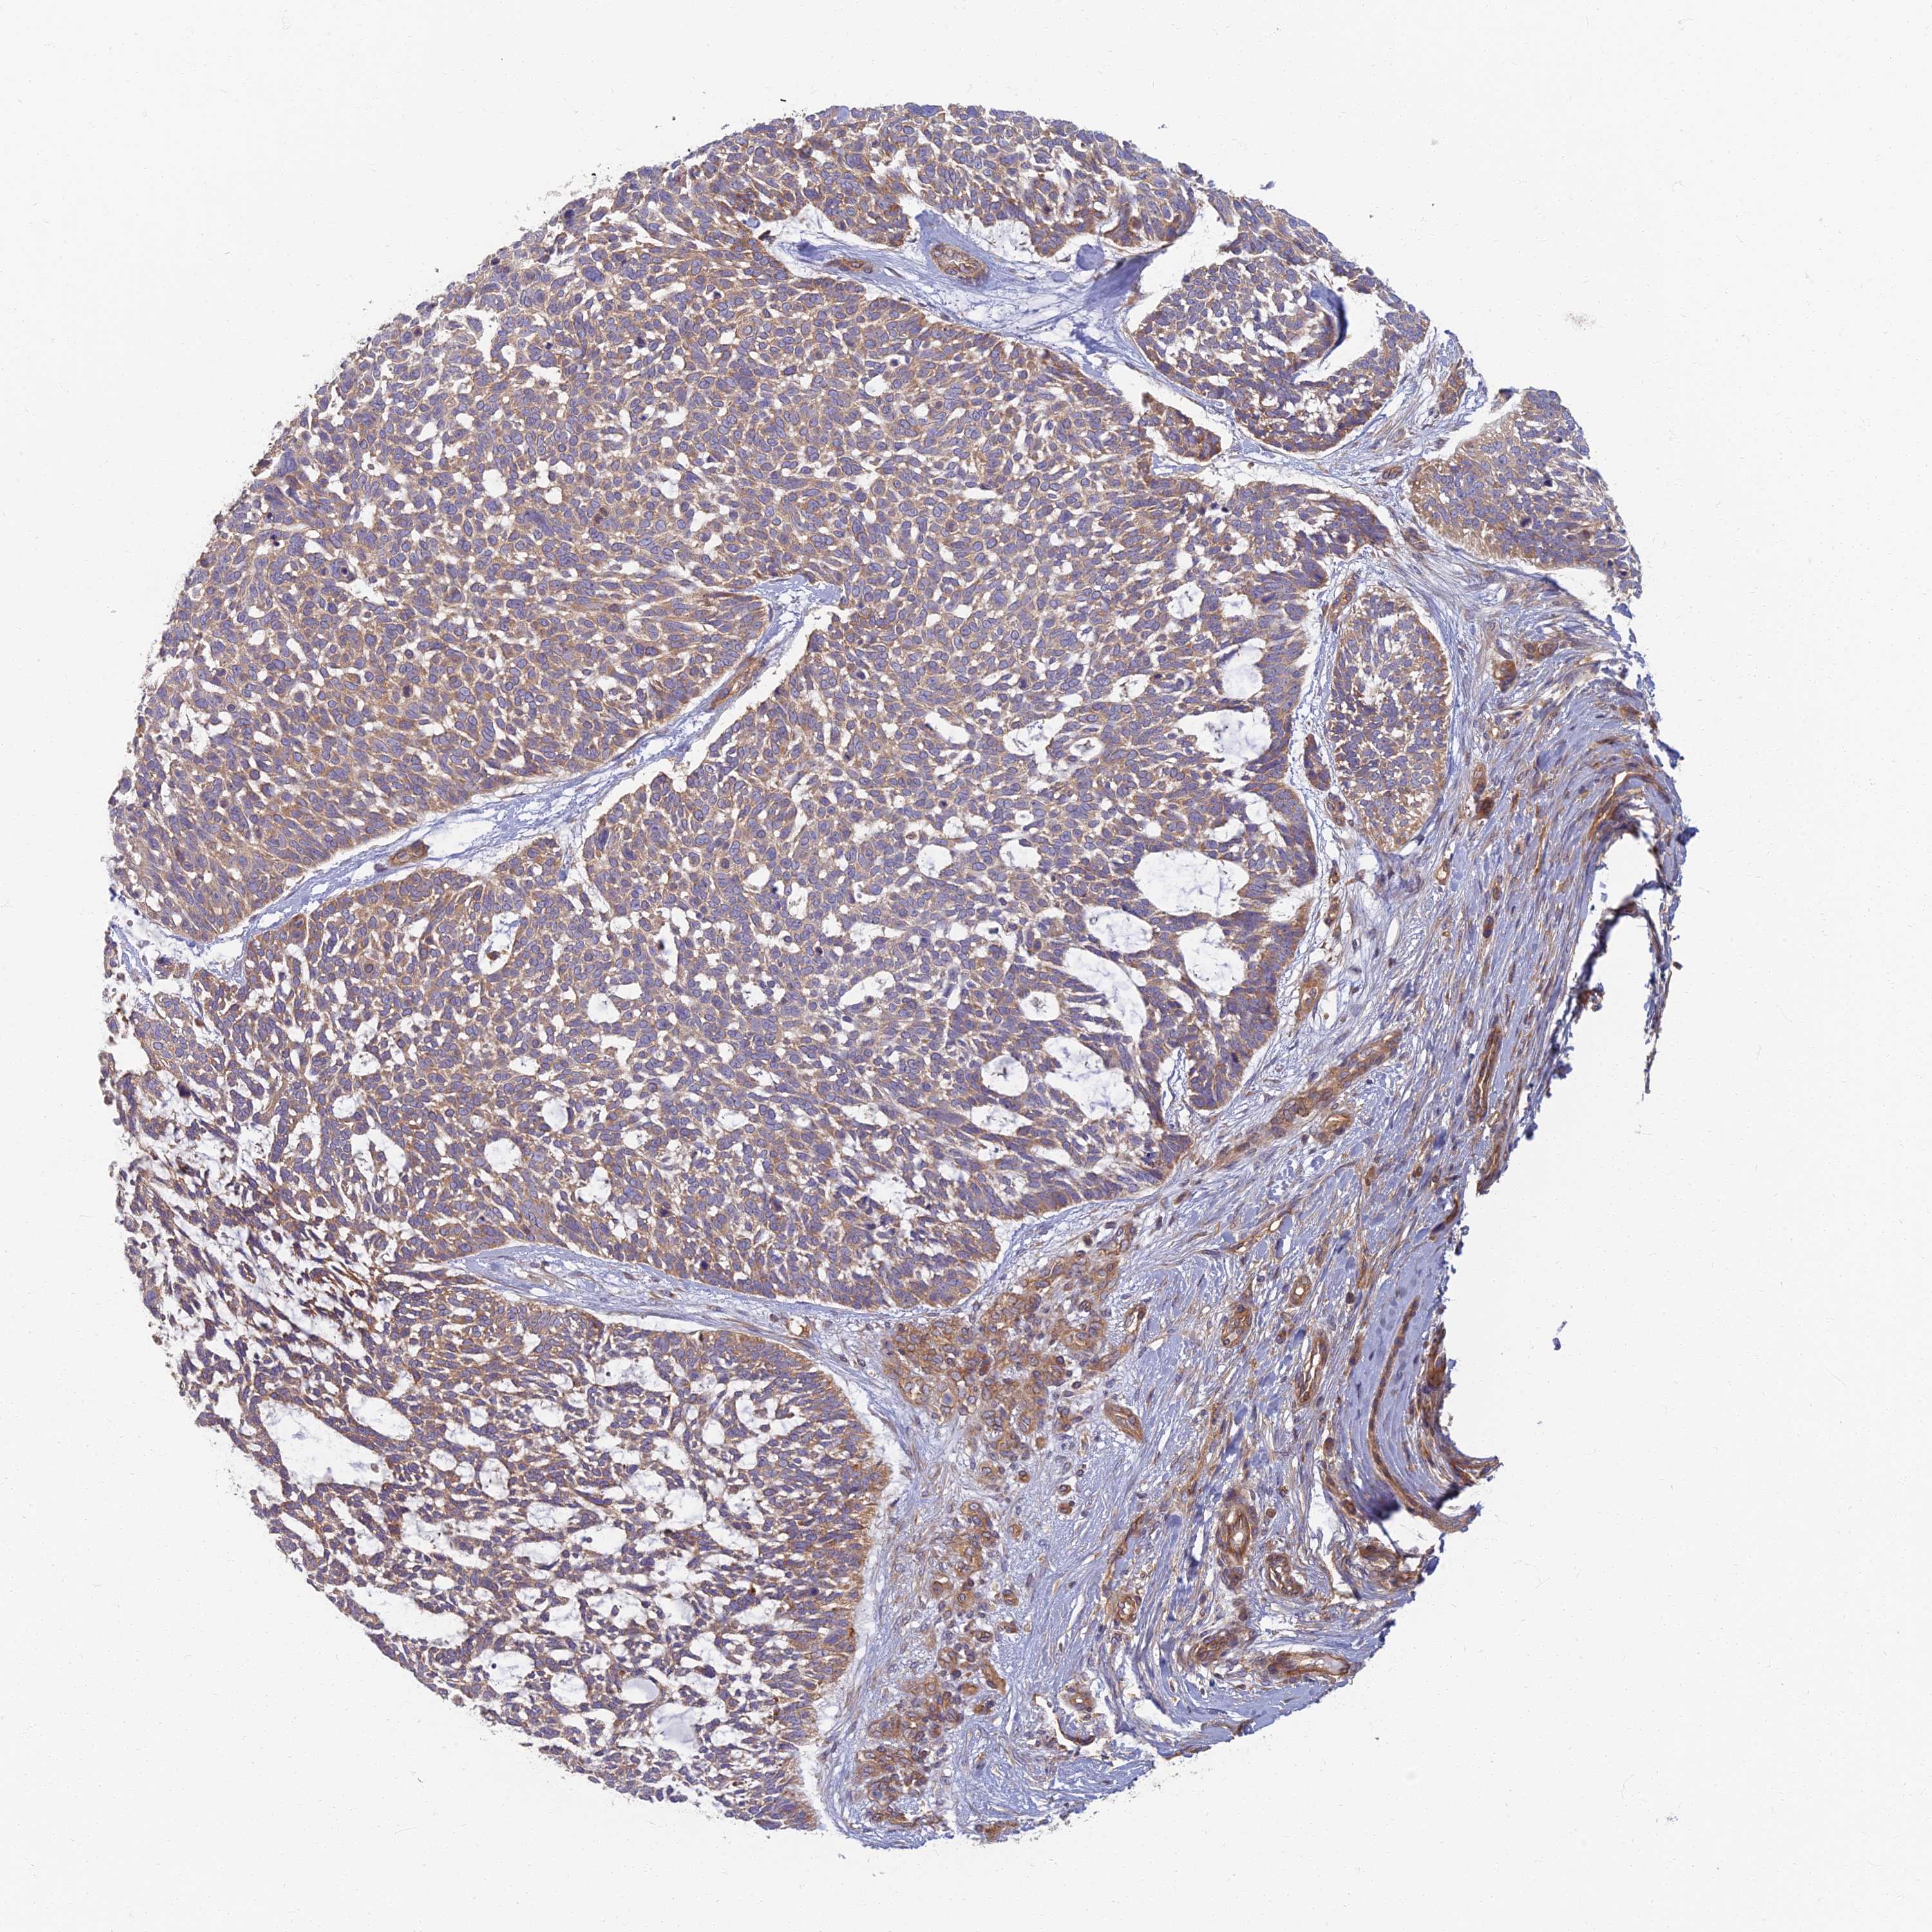

SKIN CANCER - Protein expressioni

A mouse-over function shows sample information and annotation data. Click on an image to view it in a full screen mode. Samples can be filtered based on level of antibody staining by selecting one or several of the following categories: high, medium, low and not detected. The assay and annotation is described here.

Each image is clickable and will lead to virtual microscopy that enables deeper exploration of all samples and also displays staining intensity scores, fraction scores and subcellular localization as well as patient and tissue information for each sample.

Antibody HPA044878

Staining

High

Intensity

Strong

Quantity

>75%

Location

Cytoplasmic/membranous

Basal cell carcinoma